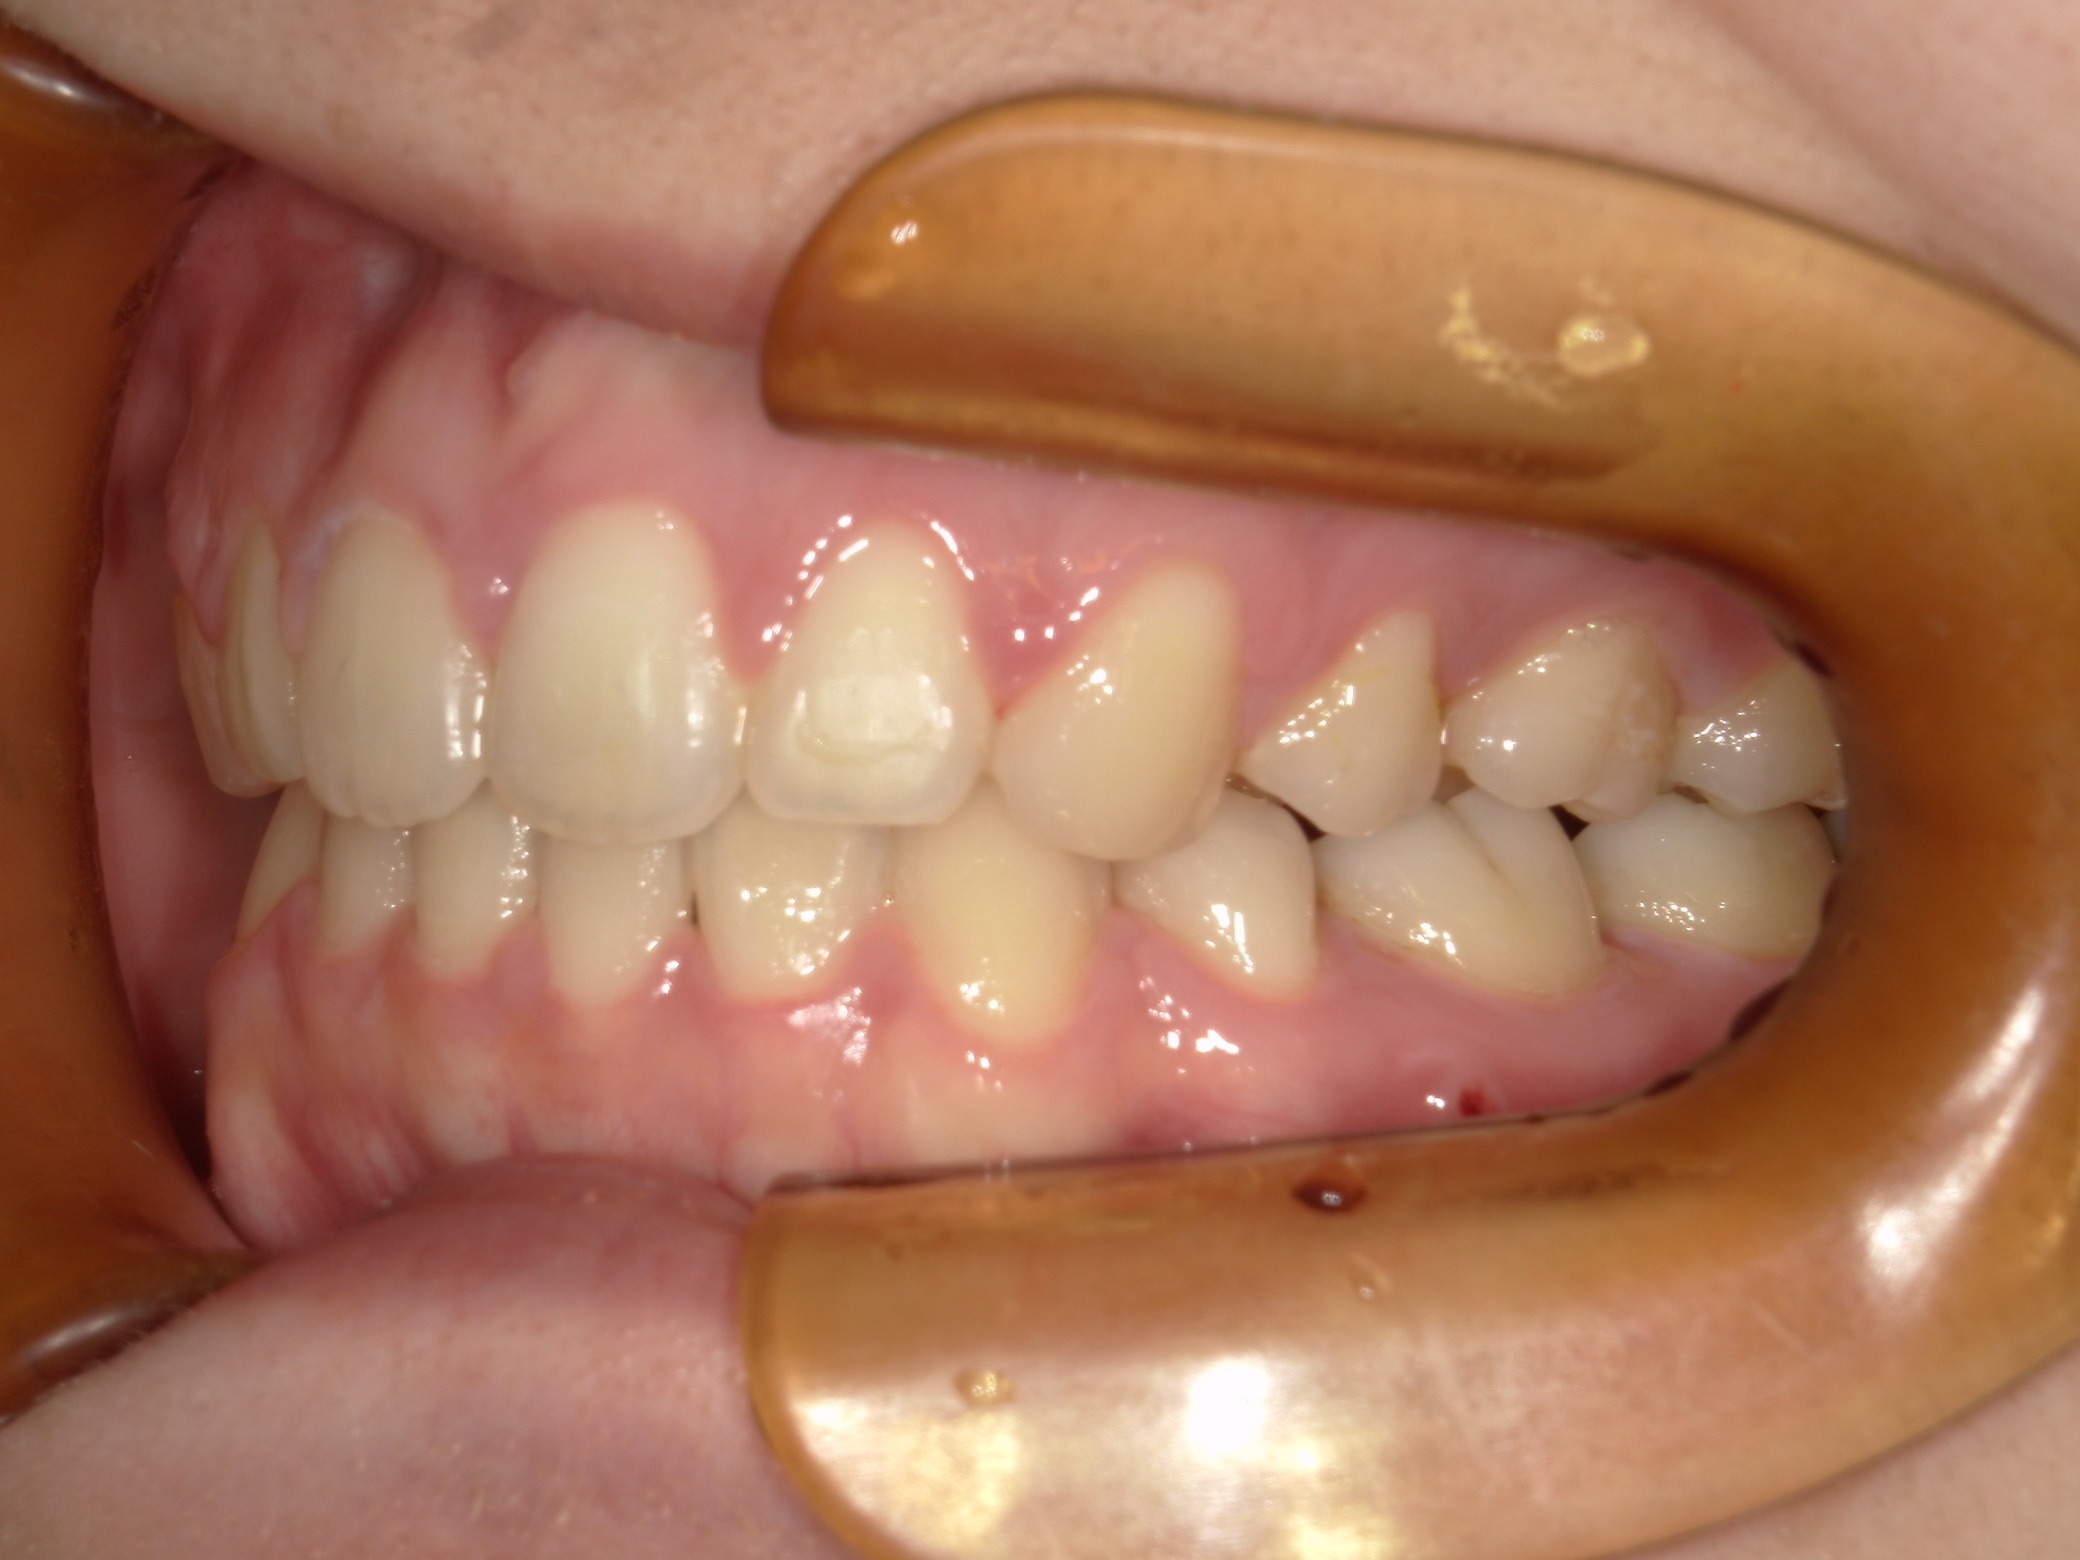

口内右

治療前

治療後